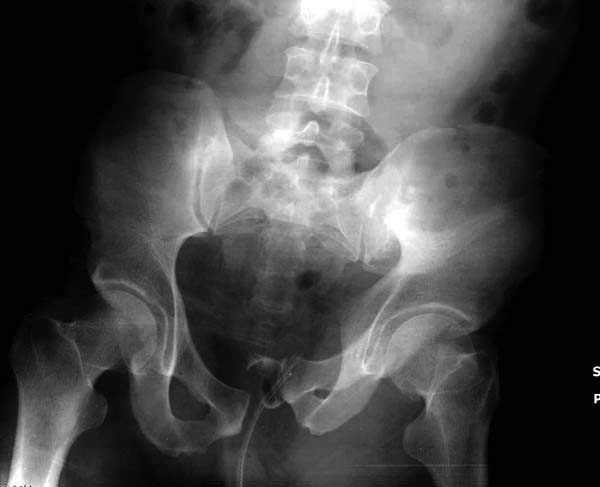

Рецидив смещения - признак несостоятельности фиксации. В первую очередь из-за ранней нагрузки, или когда имеется нестабильность в тазовом кольце. При повреждениях транссакральных структур сзади, фиксация переднего полукольца-симфиза облегчает репозицию, но не гарантирует стабильность. Нестабильное тазовое кольцо ранее или поздно срывает фиксацию симфиза.

Реконструктивные пластины слабые, и для усиления необходимо установить дополнительную верхнюю пластину или оставить передний наружный фиксатор. Предпочтительным для фиксации считаю специальную для симфиза жесткую пластину из набора Joel Matta (Stryker), которая лучше, чем остальные, создает жесткость.

Подробное изучение инлет и оутлет, а также КТ срезов, поможет разобраться в диагностике. Без обследования случай усложнится. Операция непростая, кроме технических навыков, надо иметь стандартные инструменты для операции.